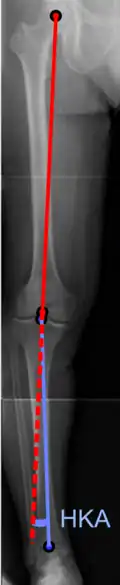

On projectional radiography, the degree of varus or valgus deformity can be quantified by the hip-knee-ankle angle,[9] which is an angle between the femoral mechanical axis and the center of the ankle joint.[10] It is normally between 1.0° and 1.5° of varus in adults.[11] Normal ranges are different in children.[12]

Hip-knee-ankle angle by age, with 95% prediction interval.[12]